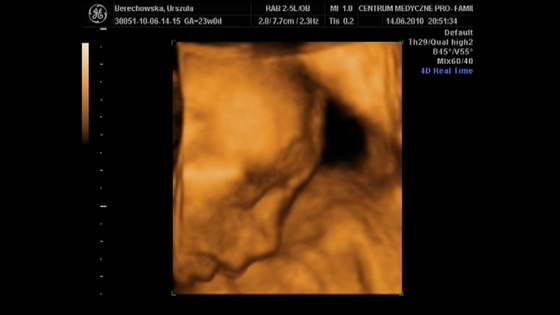

Ja na usg 3d juz byłam w 24 tyg ciąży choć powiem szczerze że spodziewałam się czegoś więcej. dzidzia.jpg

Na tym usg jednoznacznie wyszedł chłopiec no i że ma śliczny mały nosek :-)